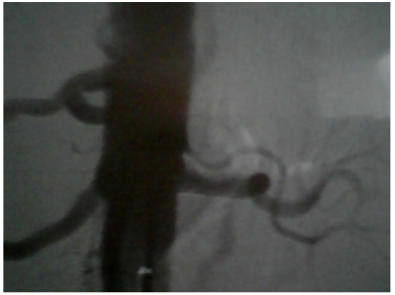

Urine test did not show albuminuria, while renal function deteriorated in the last six months: urea was increased from 25 to 49mg/dl and creatinine from 0.7mg/dl to 1.3mg /dl. In kidney ultrasound the right kidney was at 11cm while the left kidney was smaller, at 9.5cm. The triplex of the renal arteries showed a significant degree of stenosis in the left renal artery (Figures 1 & 2). The maximum velocity in doppler must not exceed 1.4 m/s while our patient has 5m/s in the left artery! Additional pathological findings are: (Figure 3)

Figure  1 Doppler of left renal artery.

The acceleration time 0,12s (AT:<0,07sec), indicative renal low flow. The patient was then subjected to magnetic angiography of renal arteries (MRA) confirming the triplex’s findings: 90% stenosis of left renal artery immediately after the outgrowth of the abdominal aorta (Figure 4). In the radioactive nephrogram, impaired left kidney function is demonstrated at 36% in the relative involvement of total renal function (split function), as opposed to the right kidney that contributes to 64% of glomerular function (Figure 5). In the same test was calculated with gates technique the GFR in the right kidney at 76.2ml/min/1,73m2,while in the left kidney 26.6ml/min/1,73m2.